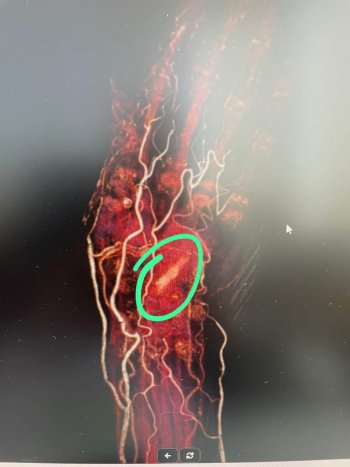

Gün geçtikçe elinin acısının arttığını ve elinin ön ve arka tarafının delinerek akıntı olmaya başladığını söyleyen Raziye Baş, “Kalça kırığı çok acı veren bir durum olmasına rağmen elimin acısından durmaz hale geldim. Tekrar hastaneye geldim. Günlerce hastanede yattım. Kolumdan film ve MR çekilmesine rağmen kimse bu film ve MR’a bakmadı. Enfeksiyon geçer diye tam 7 ay beklettiler. Kolumu kullanamaz ve yalnız başıma hayatımı sürdüremez hale geldim. Bir yakınımın tavsiyesi ile bu defa İzmir’e başka bir hekime gittim. Doktor beraberimde götürdüğüm film ve MR’ı bakar bakmaz içeride bir cisim olduğunu belirtip hemen ameliyata aldı. Elimin içinden büyük bir odun parçası çıkarıldı. Kısa sürede sağlığıma kavuştum” ifadelerini kullanarak bu duruma sebep olan kişi ve kişilerden şikayetçi olduğunu da ekledi.

İlk gittiği hastanede çekilen film ve MR’ı da paylaşarak yaşadığı acının normal bir sağlık sorunu olmadığını hatta tamamen ihmalden kaynaklandığını ileri süren Raziye Baş, “Ben ‘canım çok yanıyor elimi hareket ettiremiyorum’ dedikçe Aydın’daki doktor beni tembellikle suçladı. ’Tembel olduğun için elini hareket ettirmiyorsun’ deyip benim psikolojimi de bozdular. İnsan önündeki film ve MR’a bakmaz mı? Bana 7 ay boyunca adeta işkence ettiler” şeklinde sitem etti.